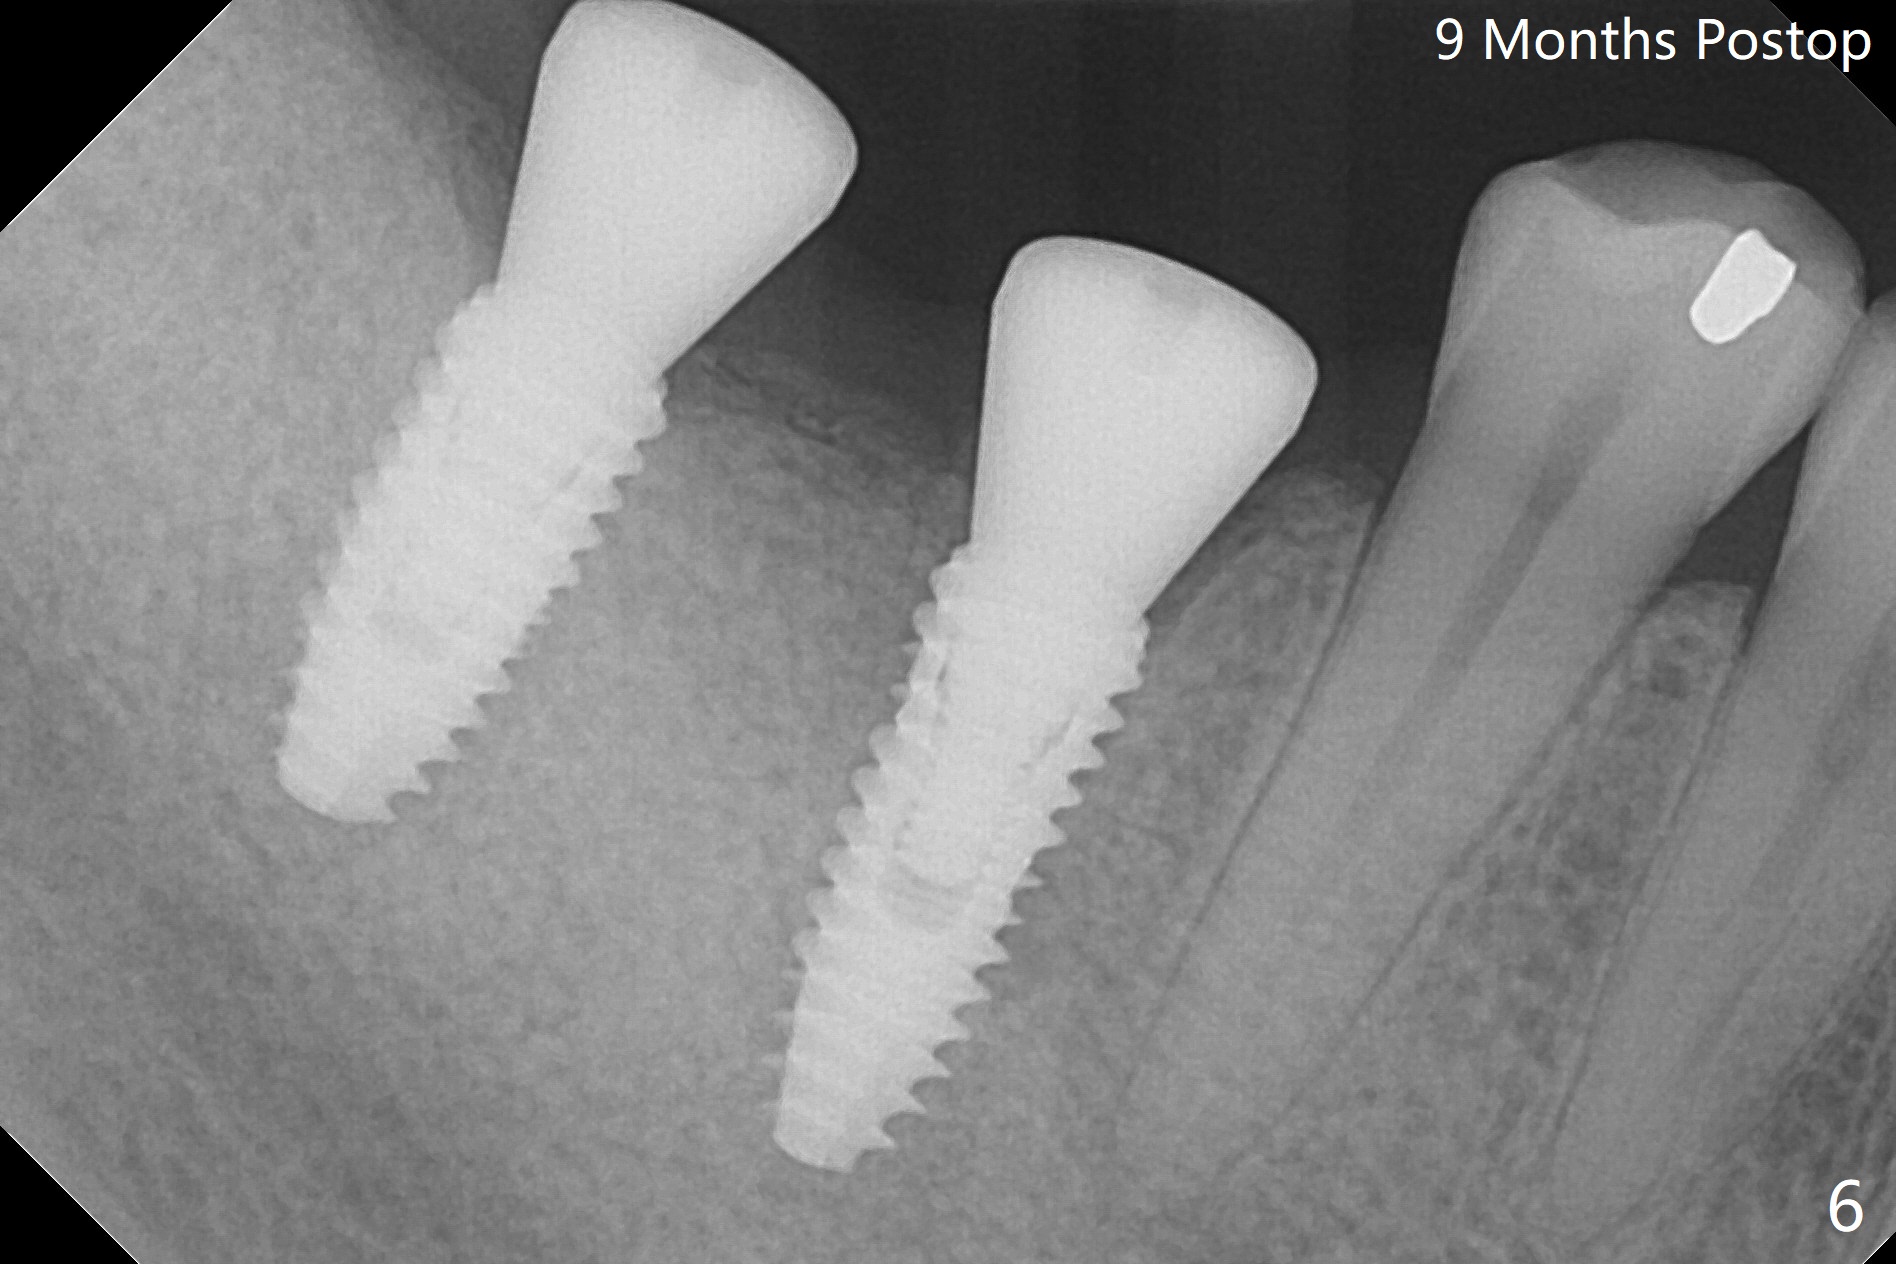

Infection is not so typical.  There is no recent postop X-ray, just 18-19 days postop.   Thanks for the reply.  We will keep watching.  The healing abutments, loose and associated with gingival inflammation, are removed 2.5 months postop (Fig.4).  There is crestal bone resorption, although the implants are stable.  The crestal bone resorption persists especially #30 distal 4 months postop (Fig.5 *).  When the implants are uncovered, there is mild bone loss distobuccal to #30 implant, consistent with early periimplantitis.  Bone graft is placed after debridement and healing abutment placement.  There appears no bone loss nearly 9 months postop (Fig.6).  The soft tissue looks healthy.  Cementation abutments (5.7x4(3) and 5.7x4.5(3) mm at #30,31, respectively) are placed for impression.  The distobuccal gingiva at #30 is hyerplastic 10 months postop (Fig.7 *, immediately before cementation), which is consistent with bone loss (Fig.8,9 * (periimplantitis)).  It is hoped that the infection will dissolve with improved oral hygiene (water pik) over the smooth final restoration.  In fact it is, i.e., the implants at #30 and 31 remain asymptomatic with the healthy gingiva 6 months post cementation (Fig.10,11).  There is mild crestal bone loss at #30 and 31 ten months post cementation (Fig.12).  Crown/implant ratio is the basis for screw loosening.  In fact the crown/abutment at #30 is loose 4 months later.  Incomplete seating of the abutment may be a culprit (Fig.12).  The gingival cuff is not healthy; a 6.8x7 mm healing abutment is placed with gingival blanching with Cetacaine and antibiotic ointment.  Next visit place a new smaller diameter abutment (4.5 or 5.2) with probably longer cuff (4 mm) or the existing abutment with no proximal contact crown, torque 25-30 Ncm and take BW with sensor 2 or PA with sensor 1.  In fact there is resistance to hand tighten a 4.5x4(4) mm healing abutment, which is due to contact with the mesial crest (Fig.13 *).  After use of 5.5 and 6.0 mm profile drills, the 6.8x7 mm healing abutment is reseated.  The latter appears to contact the mesial crest (Fig.14).  Later a 6x5 mm healing abutment is placed.  New crowns with new abutments are delivered 2 years 3 months postop (post Coronavirus lockdown).